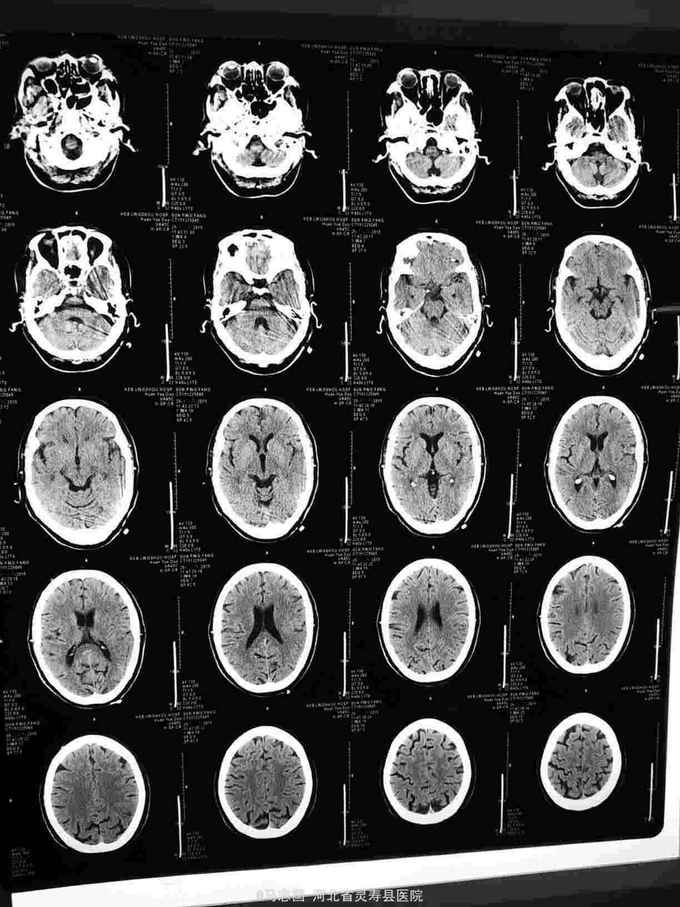

患者老年女69岁,高血压,糖尿病病史。主因意识不清2小时入院,患者缘于2小时前干农活时,突然意识不清,跌倒于地,右侧肢体抽搐,无恶心呕吐,当地未于治疗,急打120接入院,急诊测血压180/110mmhg,血糖14mmol/l,头CT未见明显异常,收入院

体温36.4℃,脉搏58次/分,呼吸19次/分,血压151/87mmhg,神志模糊,言语不能,眼动不配合,双瞳孔对光反射灵敏,双肺呼吸音清,未闻及杂音,心音低钝,左侧肢体可见活动,右上肢肌张力高,右巴氏征阳性。左巴氏征阴性。